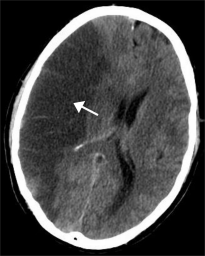

Udar krwotoczny mózgu, inaczej wylew krwi do mózgu - z uszkodzonych naczyń krwionośnych krew wylewa się bezpośrednio do mózgu lub przestrzeni znajdującej się pomiędzy mózgiem a czaszką. Krew poza naczyniami całkowicie niszczy tkanki, z którymi się styka.